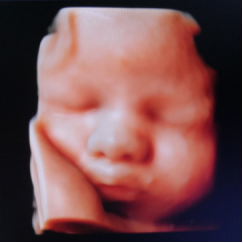

产科四维超声检查